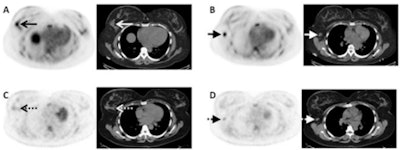

Images are from a 43-year-old woman with invasive lobular breast cancer. Axial fluciclovine-PET/CT (A) demonstrates a fluciclovine-avid (SUV 4.9) primary right breast malignancy (arrows). Axial fluciclovine-PET/CT (B) shows a fluciclovine-avid (SUV 5.8) right axillary nodal metastasis (short arrows). Axial FDG-PET/CT (C) shows near background FDG avidity (SUV 1.8) in the right breast malignancy (dashed arrows). Axial FDG-PET/CT (D) shows only mild FDG avidity (SUV 2.8) in the right axillary nodal metastasis (short dashed arrows). Image courtesy of Dr. Gary Ulaner and SNMMI.In the comparison of the two radiotracers, fluciclovine and FDG recorded similar results for tumor volume. However, fluciclovine achieved greater avidity than FDG in cases of invasive lobular carcinoma.

Among the 14 patients who underwent both fluciclovine and FDG imaging, the median SUVmax for fluciclovine avidity (6.1, range: 4.5-10.9) was significantly greater than FDG (3.7, range: 1.8-6.0) in four cases (28%) of primary invasive lobular carcinoma.

However, FDG's median SUVmax (10, range: 3.3-43.5) outperformed fluciclovine (6.8, range: 3.6-9.9) in 10 cases of primary invasive ductal carcinoma.